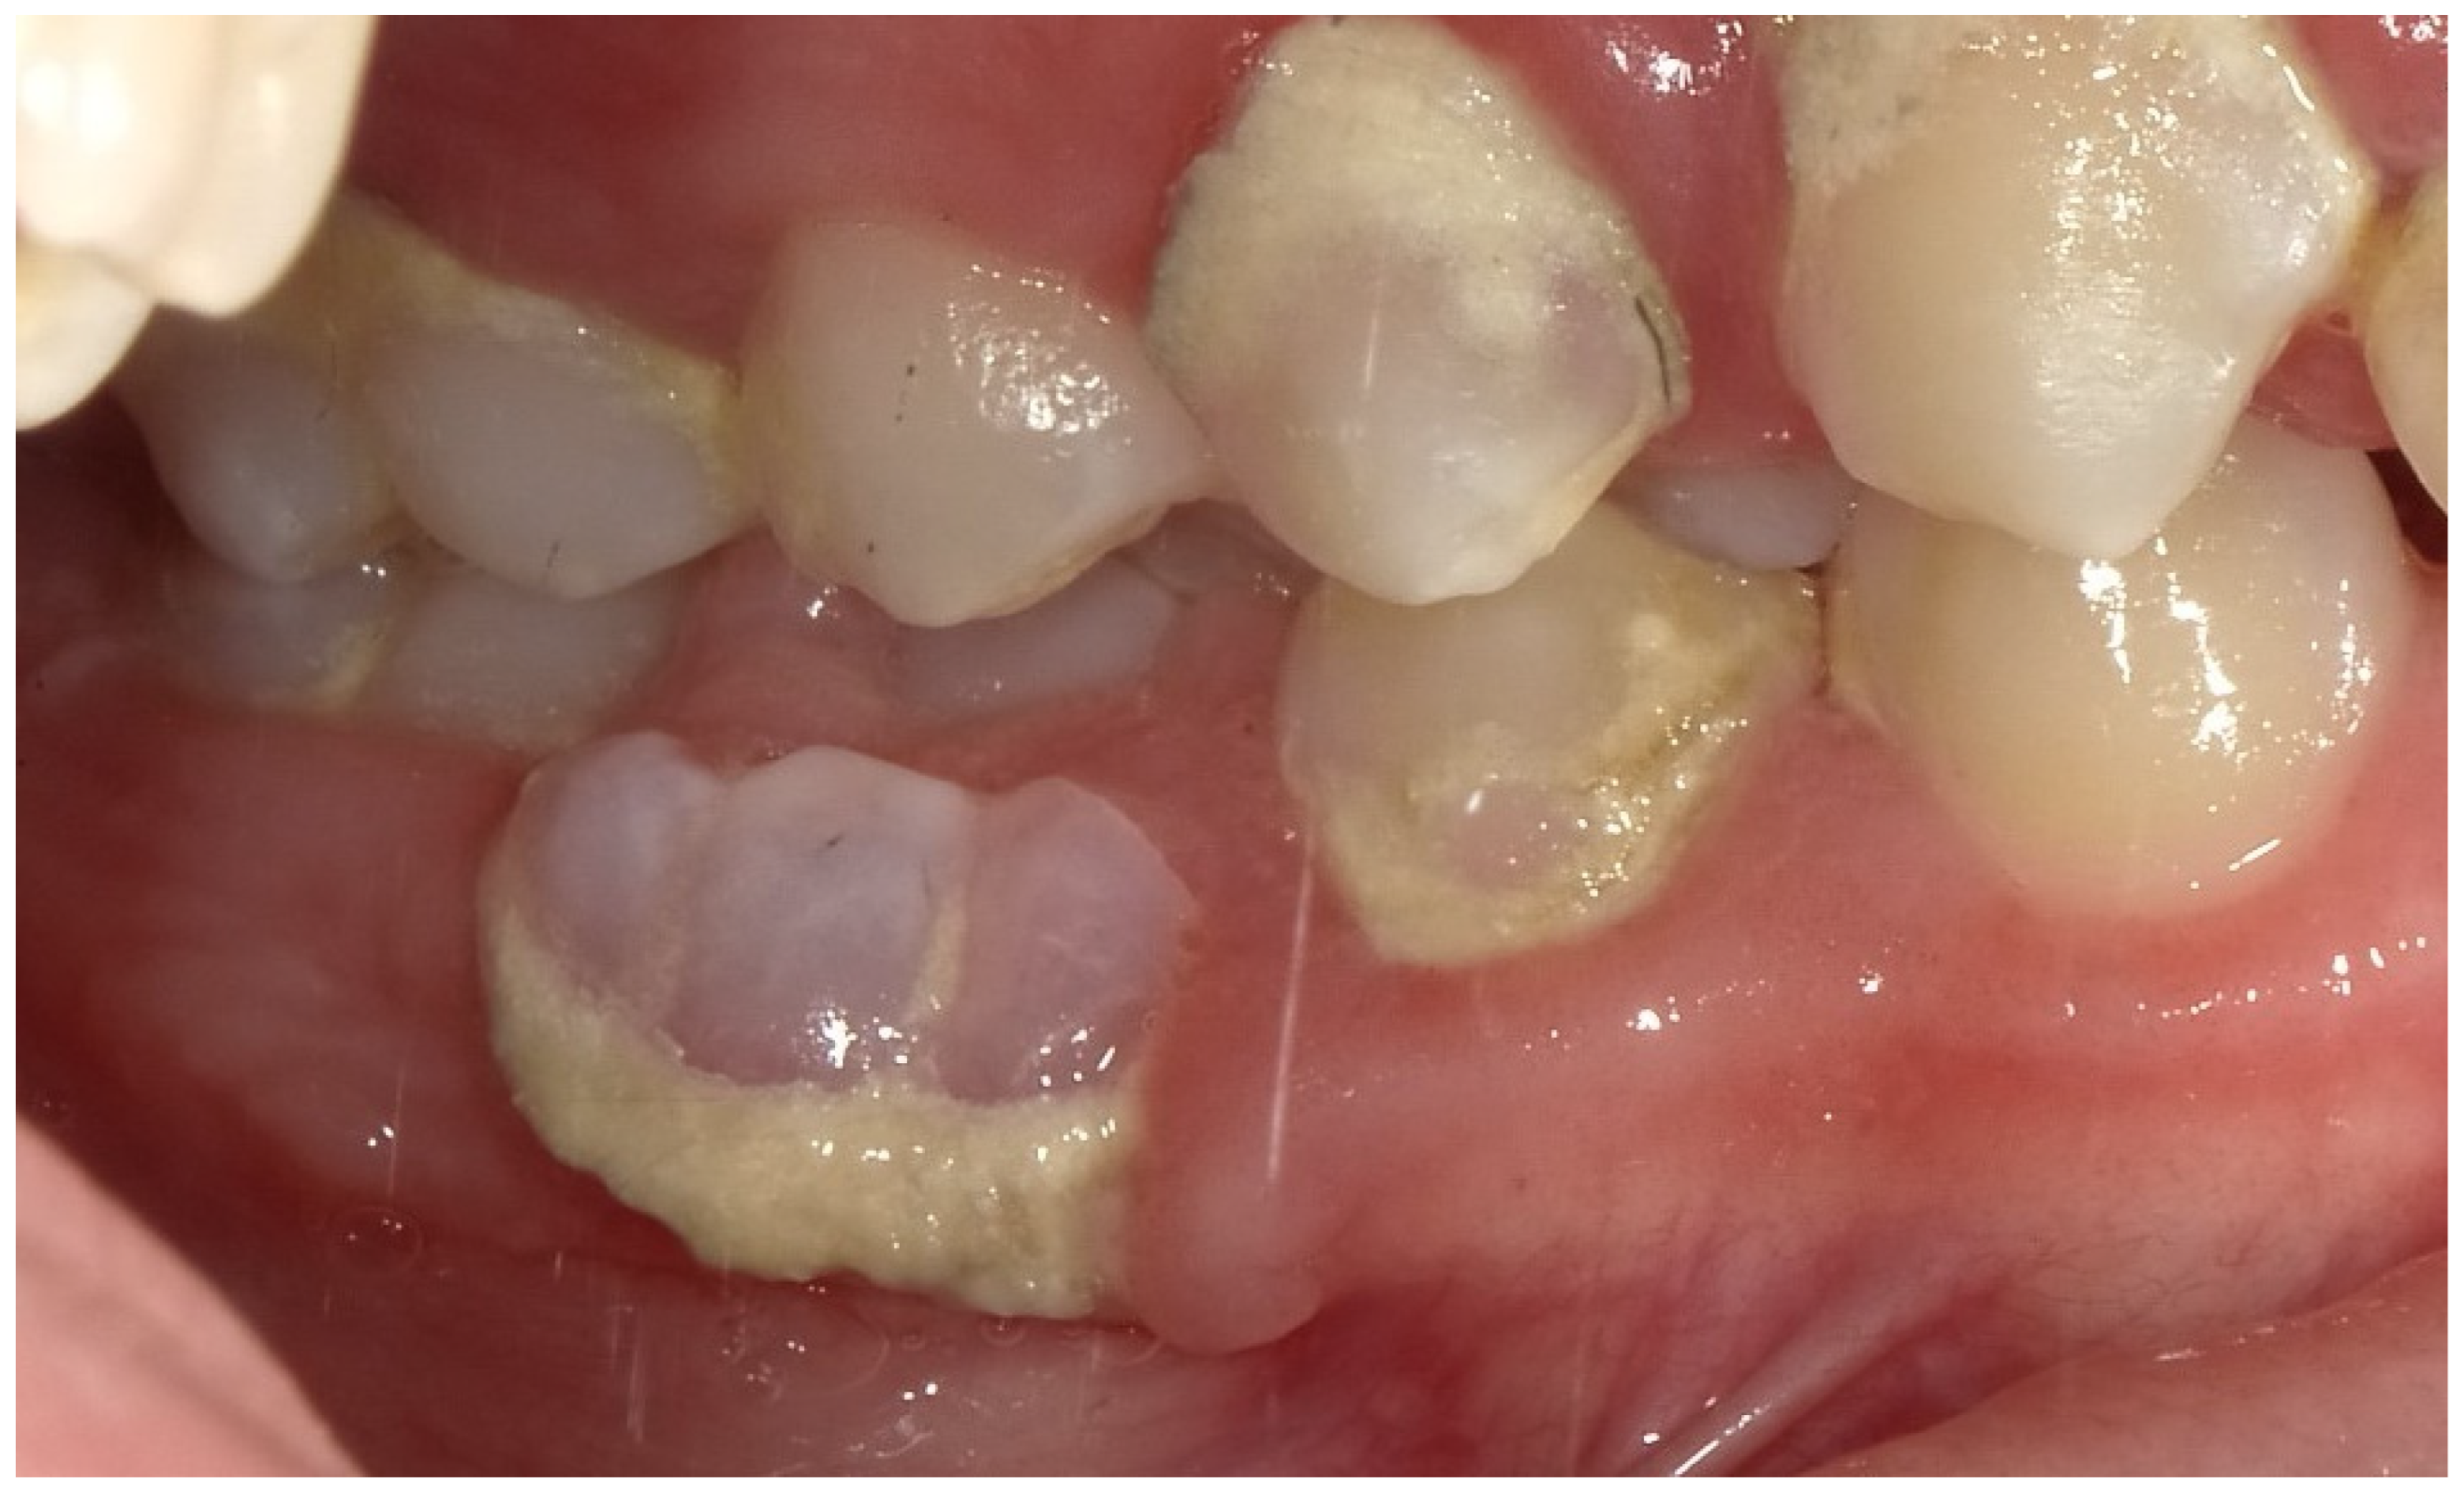

2.2. Clinical Findings

2.3. Diagnostic Assessment

2.4. Therapeutic Intervention

2.5. Follow-Up and Outcomes